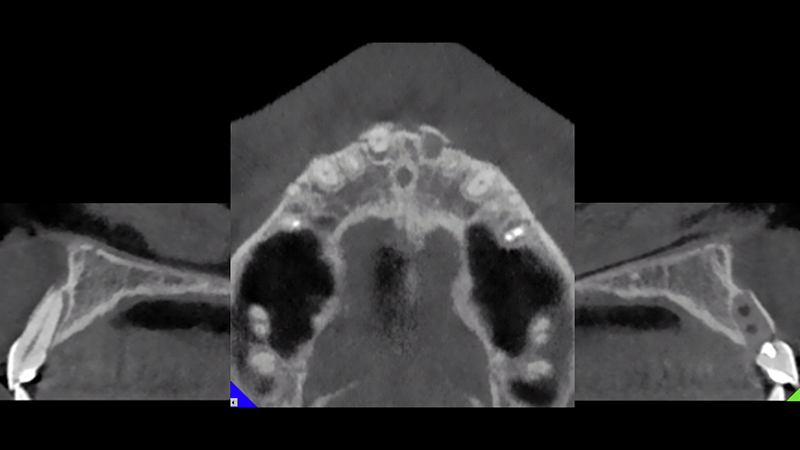

Per un trauma frontale, una paziente di 24 anni con sorriso gengivale, perde il dente 2.1. Il dente 1.1 è dislocato palatalmente e il dente 1.2 presenta un danno al margine incisale (Fig. 2a, Fig. 2b). La CBCT mostra una frattura in entrambe le placche vestibolari ossee, in corrispondenza dei due incisivi centrali superiori (Fig. 3).

CBCT dopo il trauma

Fig. 3 - CBCT dopo il trauma